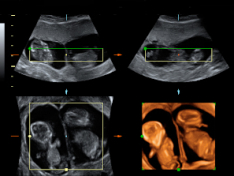

Ecografía 2D y 3D de embarazo gemelar

Imagen de un embarazo gemelar que recoge tres ecografías 2D y una en 3D. Los cuatro ultrasonidos demuestran que los bebés están alojados en bolsas independientes con placentas también independientes. Y la membrana que separa los fetos es muy gruesa, según se aprecia en la imagen...